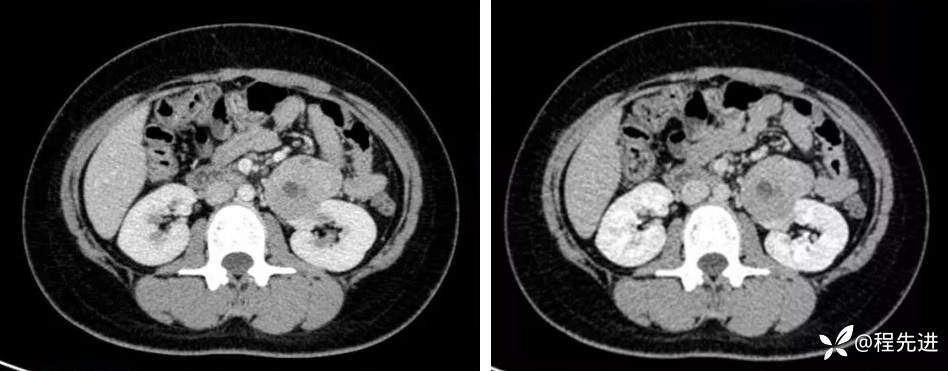

髓质期,延迟期: